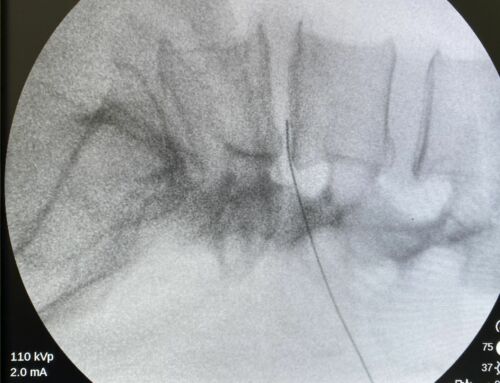

El tratamiento intrarticular con ozono está indicado para mejorar los síntomas derivados de la artrosis de rodilla, o sea, el dolor, la inflamación, la rigidez y mejorar con ello la funcionalidad y calidad de vida de la persona.